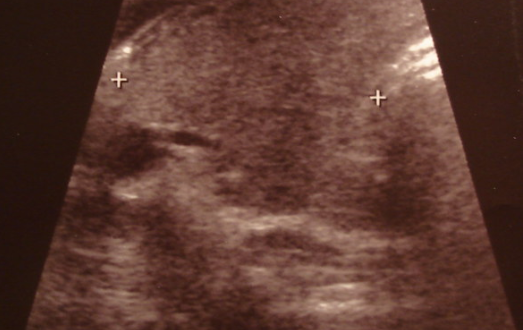

3. 갑상선의 초음파 검사

일반적으로 갑상선 초음파 검사에서 갑상선의 크기 나 용종, 암이 없는지 등을 확인합니다.